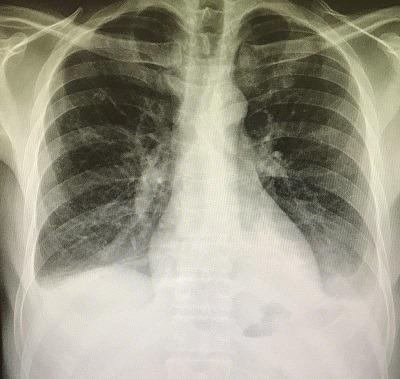

This case has interesting images of huge hydro pneumoperitoneum. It is a rare view in the medical practice and a good point to learn one of the complications of perforated duodenal ulcer and failure of omental patch operation. We reported a case of acute abdominal pain with hydro pneumoperitoneum that appeared as an air fluid line in X-ray. The patient had an omental patch surgery. Two days after the operation he got severe abdominal pain. The X-ray images showed significant huge hydro pneumoperitoneum. He underwent urgent surgical intervention for exploration that detected a large amount of gases, a biliary free fluid and a leak from duodenal ulcer. Omental buttressing was then performed.

该病例有巨大气腹积气的有趣影像。这在医学实践中是一种罕见的情况,也是了解十二指肠溃疡穿孔和网膜修补手术失败的并发症之一的好机会。我们报告了一例急性腹痛伴气腹积气的病例,X线显示为气液平面。该患者接受了网膜修补手术。术后两天,他出现剧烈腹痛。X线影像显示有明显的巨大气腹积气。他接受了紧急手术探查,发现大量气体、无胆汁的液体以及十二指肠溃疡渗漏。随后进行了网膜支撑术。